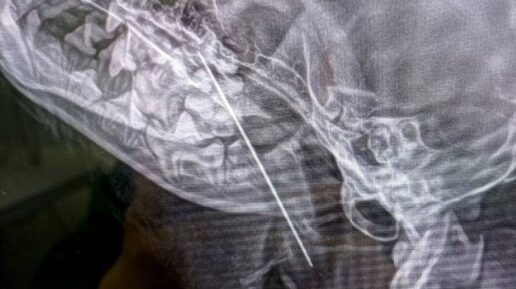

Крупную швейную иглу достали из щенка йоркширского терьера в Москве

Столичные ветеринары Тушинской клиники извлекли большую швейную иглу из 10-месячного щенка йоркширского терьера по кличке Маруся. Об этом во вторник, 28 января, сообщили в пресс-службе «Мосветобъединения». Собаку привезли в клинику с жалобами на кашель. Незадолго до этого Маруся стащила с хозяйской кухни кусок форели и съела его. Сначала хозяева предположили, что она подавилась рыбной костью. Однако врачи сделали щенку рентген и выяснили, что в мягких тканях его глотки застряла игла. Пушистую пациентку...